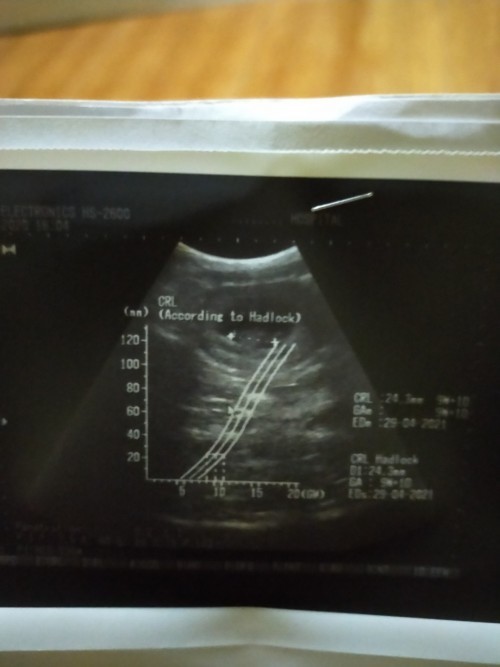

ซาวด์ครั้งแรกท้อง11วีคก้เจอแบบนี้เรยค่ะเสียใจกังวลมากค่ะอีก2อาทิตย์หมอนัดอีกเรายังมีหวังที่จะเจอตัวน้องยุไหมคะสอบถามแม่ๆที่เจอเรื่องแบบนี้หน่อยค่ะขอบคุณสำหรับคำตอบค่ะ😔

7wก็ยังใม่เจอเหมือนกันคะ หมอนัดซาวอีกรอบตอน18w ยังกังวนว่าเขาจะยังยุไหม